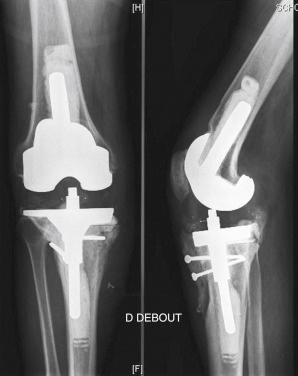

A 72-year-old woman underwent a total knee arthroplasty (TKA) for primary osteoarthritis that was revised to a hinged TKA 12 years later because of loosening. Twelve months after the revision TKA, she was referred to our center. A postoperative infection occurred 3 weeks after the index implantation. The knee was reoperated to provide surgical débridement. A fistula persisted postoperatively, and the patient continued to have severe pain. Early loosening was observed on sequential radiographs ( Fig. 35.1 ). Persistent infection was diagnosed after culture of a knee aspirate grew Staphylococcus aureus that was sensitive to methicillin.

FIGURE 35.1, Case 1: Standard preoperative radiographs. A, Anteroposterior (AP) view. B, AP view centered on the tibial cortical defect